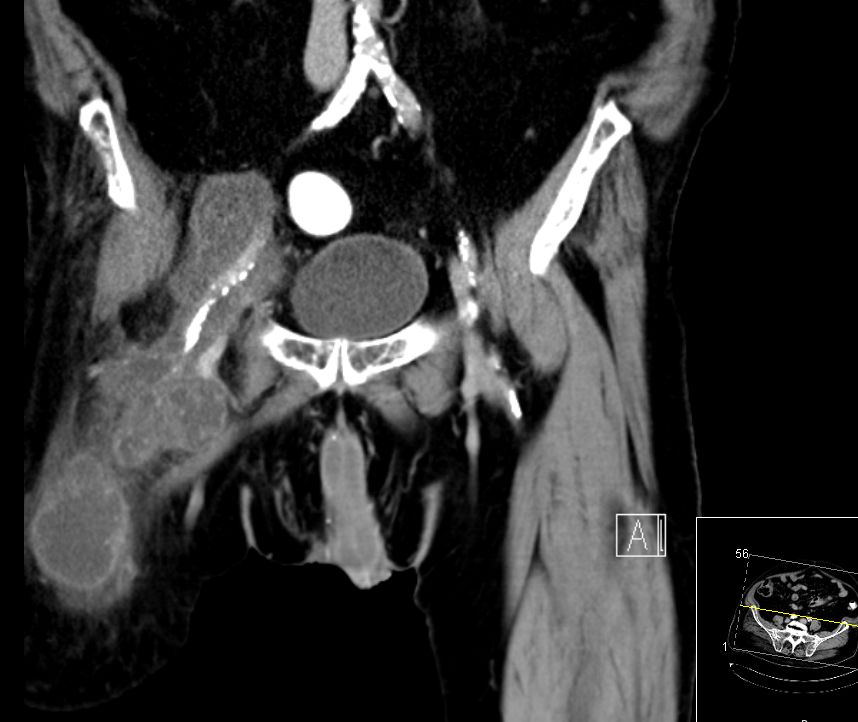

74-jähriger Mann, der vor 2 Jahren eine Beinamputation rechts wegen eines Chondrosarkoms der Tibia hatte. Jetzt ausgedehnte Knoten in der rechten Leiste. |